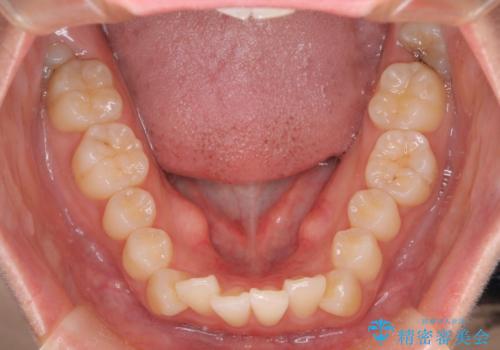

- 出っ歯、ガタツキ、噛み合わせが気になるとのことで来院された患者様です。

小臼歯を抜歯することでスペースを作り、前歯を下げて口元を下げ、Eラインを改善する治療方針としました。